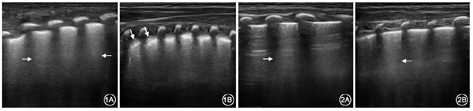

入院时5例患儿均出现局部胸膜线的病变,如欠光滑、增厚、模糊或消失,同时均出现不同程度的肺水肿征象,超声表现为密集程度、区域分布不一的B线,例5于双肺后上区、后下区胸膜下出现局灶性肺实变,实变肺组织内可探及充气支气管征象,与肺间质综合征改变毗邻、并存,见图1。患儿病程中、出院前复查肺部超声提示,与入院当日相比,肺水肿不同程度减轻,肺实变区消失,肺泡间质综合征程度明显减轻,见图2。

COVID-19患者病变部位大部分位于双肺外带胸膜下,病灶多发,但成人分布更广泛、弥散[6],成人COVID-19主要肺部病变的超声声像图特征为肺间质综合征、肺实变和胸腔积液[7]。当炎症引起肺内气体减少、肺泡内含液量增多,间质及周围血管水肿,超声图像上表现范围不等的B线,能反映肺脏含水量增加[8],随着病情的进展,渗出液增多,肺泡塌陷,纤维组织增生,形态学上出现不同程度肺实变。本组5例患儿肺部超声均提示有不同程度肺水肿改变,其中3例肺部超声表现为散在B线,部分肺区发现融合B线,提示患儿存在轻度肺水肿;1例患儿部分肺区可见密集的B线呈火箭征,考虑为肺间质综合征,提示该患儿存在中度的肺水肿,这也印证了关于肺水肿是COVID-19主要的病理表现这一说法[9];1例患儿双肺后区可见胸膜下小片状实变,周围组织呈肺间质综合征,其声像图表现与新生儿呼吸窘迫综合征类似,但病变范围较局限,仅累及双肺后区。住院第6天复查超声双肺未见实变区,病灶较前减小,双肺后下区可见多发密集分布的B线,呈肺泡间质综合征表现。本组5例患儿均出现不同范围的胸膜线增厚、模糊,考虑与病灶主要位于胸膜下或肺野外带,炎性渗出累及胸膜导致局部的胸膜反应[10],异常肺部超声征象在肺下叶为主,与余成成等[11]报道基本一致,这可能与病理性肺炎早期累及终末细支气管和呼吸性细支气管等病理机制有关。病程中患儿肺部B线逐渐减少,胸膜线和A线恢复,实变区消失,证实临床操作中肺部超声对病情评估的可行性。